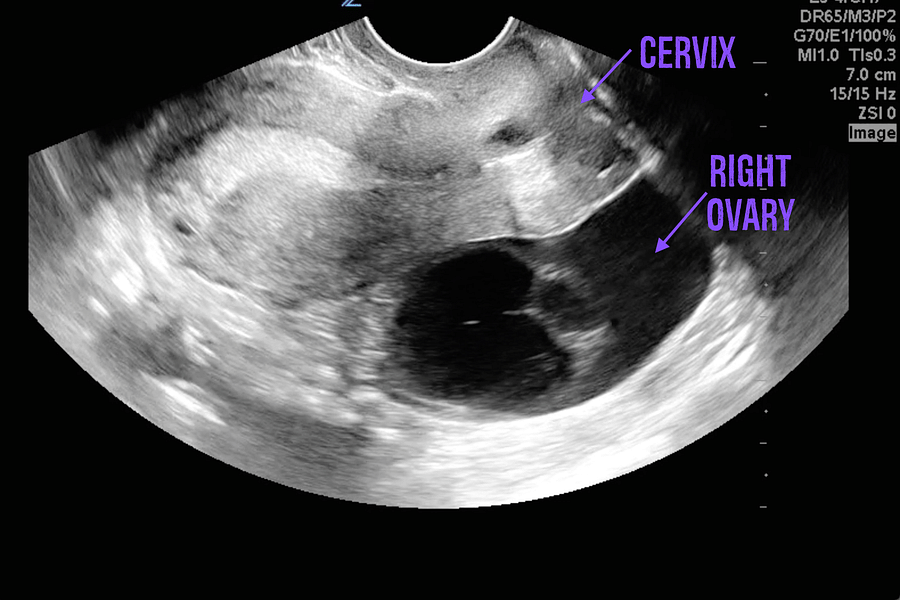

Sometimes what seems like a run-of-the-mill period symptom could be a sign of something more significant. For example, extremely painful cramps could indicate conditions like endometriosis or fibroids. Similarly, if you're experiencing cramps but no bleeding, it might be worth exploring the possibility of pregnancy or an ovarian cyst.